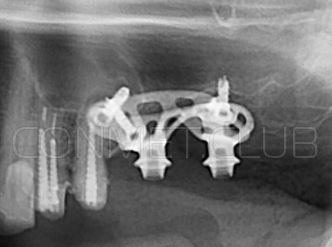

2. После этого произвели компьютерное моделирование самого имплантата и фиксирующих элементов. Примечательно, что в абатментах, использовался отлично зарекомендовавший себя и проверенный десятилетиями интерфейс КОНМЕТ! В результате получили несколько специальных файлов, позволяющих не только сделать сам имлантат, но еще до операции изготовить и сами зубы. Данные файлы передали в изготовление на специальном 3D оборудовании.

Имплантат напечатали из особого, биосовместимого, медицинского титана на предприятии имеющим соответствующую медицинскую лицензию. Толщина имплантата составила 0,8 мм, а вес всего несколько грамм!

Первый вывод к которому мы пришли, это то, что для данных конструкций имплантатов сохранять внутренний интерфейс с шестигранником и конусом Морзе нецелесообразно из-за ограничения возможностей современной 3D печати титана. Кроме того, техническая обработка после 3D печати такого интерфейса представляет значительные трудности и ведет к неоправданному увеличению цены. Поэтому пришли к единодушному мнению, что лучший вариант-это опорные элементы полностью повторяющие абатменты-мультиюниты.

Посмотрите на небольшом клиническом примере новый подход к конструированию имплантата по сравнению с имплантатами описанными в начале этой статьи.